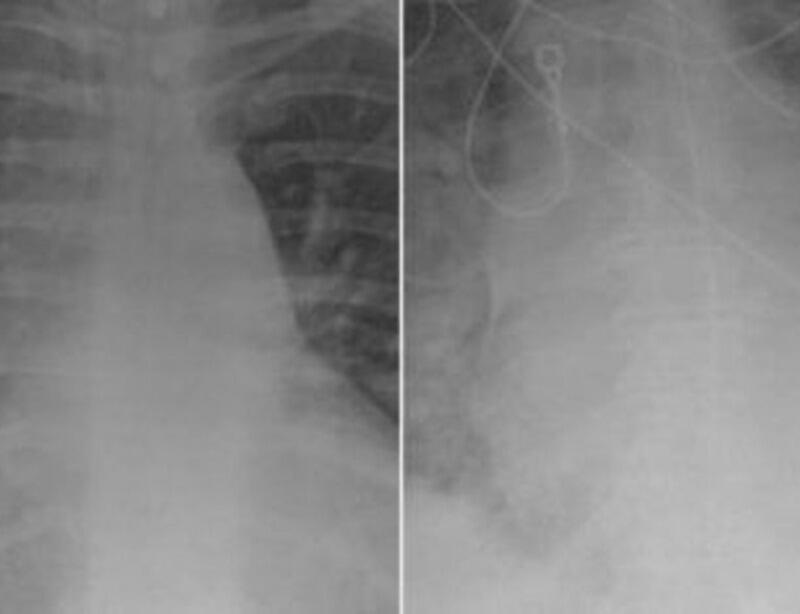

Uma foto, que está circulando nas redes sociais, mostra a comparação de dois raios-X de pacientes infectados pela Covid-19. Em uma das chapas, aparece um pulmão de uma pessoa vacinada, enquanto na outra imagem é possível ver um pulmão sem vacina.

Na imagem do indivíduo vacinado, é possível observar um pulmão mais “limpo”. Já a foto do paciente não imunizado, a foto do órgão está turva.

O médico Ghassan Kamel, diretor da UTI Médica do Hospital SSM Health SLU, localizado em St. Louis, em Missouri, nos Estados Unidos, afirmou que a coloração mais densa do pulmão indica infecção por bactéria, muco ou secreções. De acordo com ele, para se tratar um paciente não vacinado, ele possivelmente precisaria de internação. “Definitivamente, pelo menos, exigiriam oxigênio e às vezes exigiriam mais do que apenas oxigênio, como ventilador ou serem intubados com ventilação mecânica, sedados e basicamente com suporte de vida”, disse, em entrevista à revista People.

Segundo Kamel, pacientes vacinados e que testam positivo para o coronavírus geralmente não requerem os cuidados intensivos ou mesmo dar entrada na UTI, a não ser que tenham alguma doença pré-existente ou que sejam imunocomprometidos.